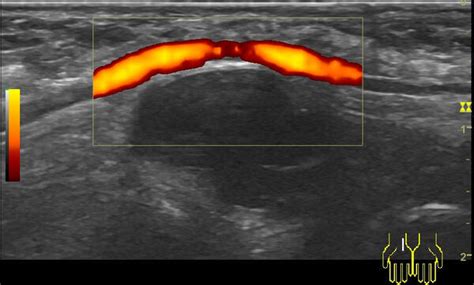

Adneksalna torzija je zvitje ali zasuk jajčnika in/ali jajcevoda, kar lahko vodi v oteklino jajčnika, zaustavitev dotoka krvi v jajčnik, odmiranje tkiva in nekrozo. Bolečina je nenadna, zelo močna, po analgetikih ne popušča in je na eni strani. Pred zasukom je v jajčniku običajno cista. V diagnostiki nam pomagajo preiskave krvi, ultrazvok in laparoskopija.